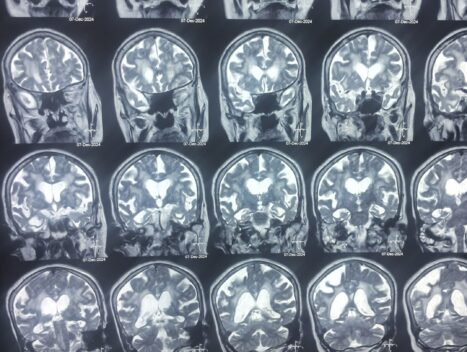

Examaination of Symptoms, Analysis of Brain Scan etc

Understanding Dementia: The Significance of Lobular Study in Managing Symptoms